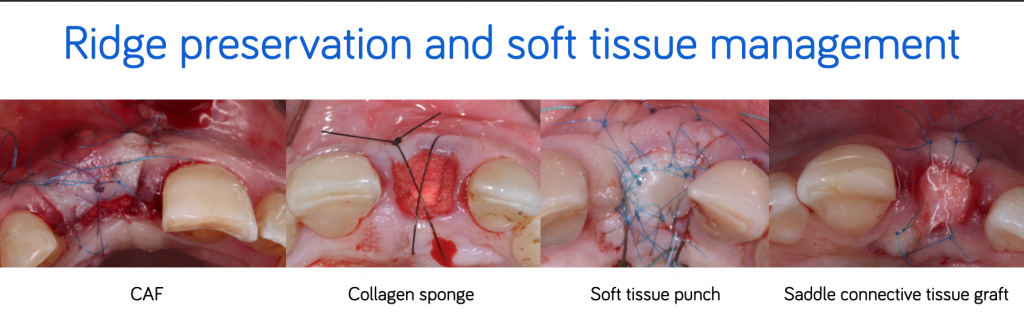

Ridge preservation and soft tissue management

To protect the blood clot and the filling material and to optimize the preservation of the tissue volume, several surgical techniques make it possible to close the socket:

- The coronally advanced flap (CAF)

- The collagen sponge

- The soft tissue punch

- The saddle connective tissue graft.